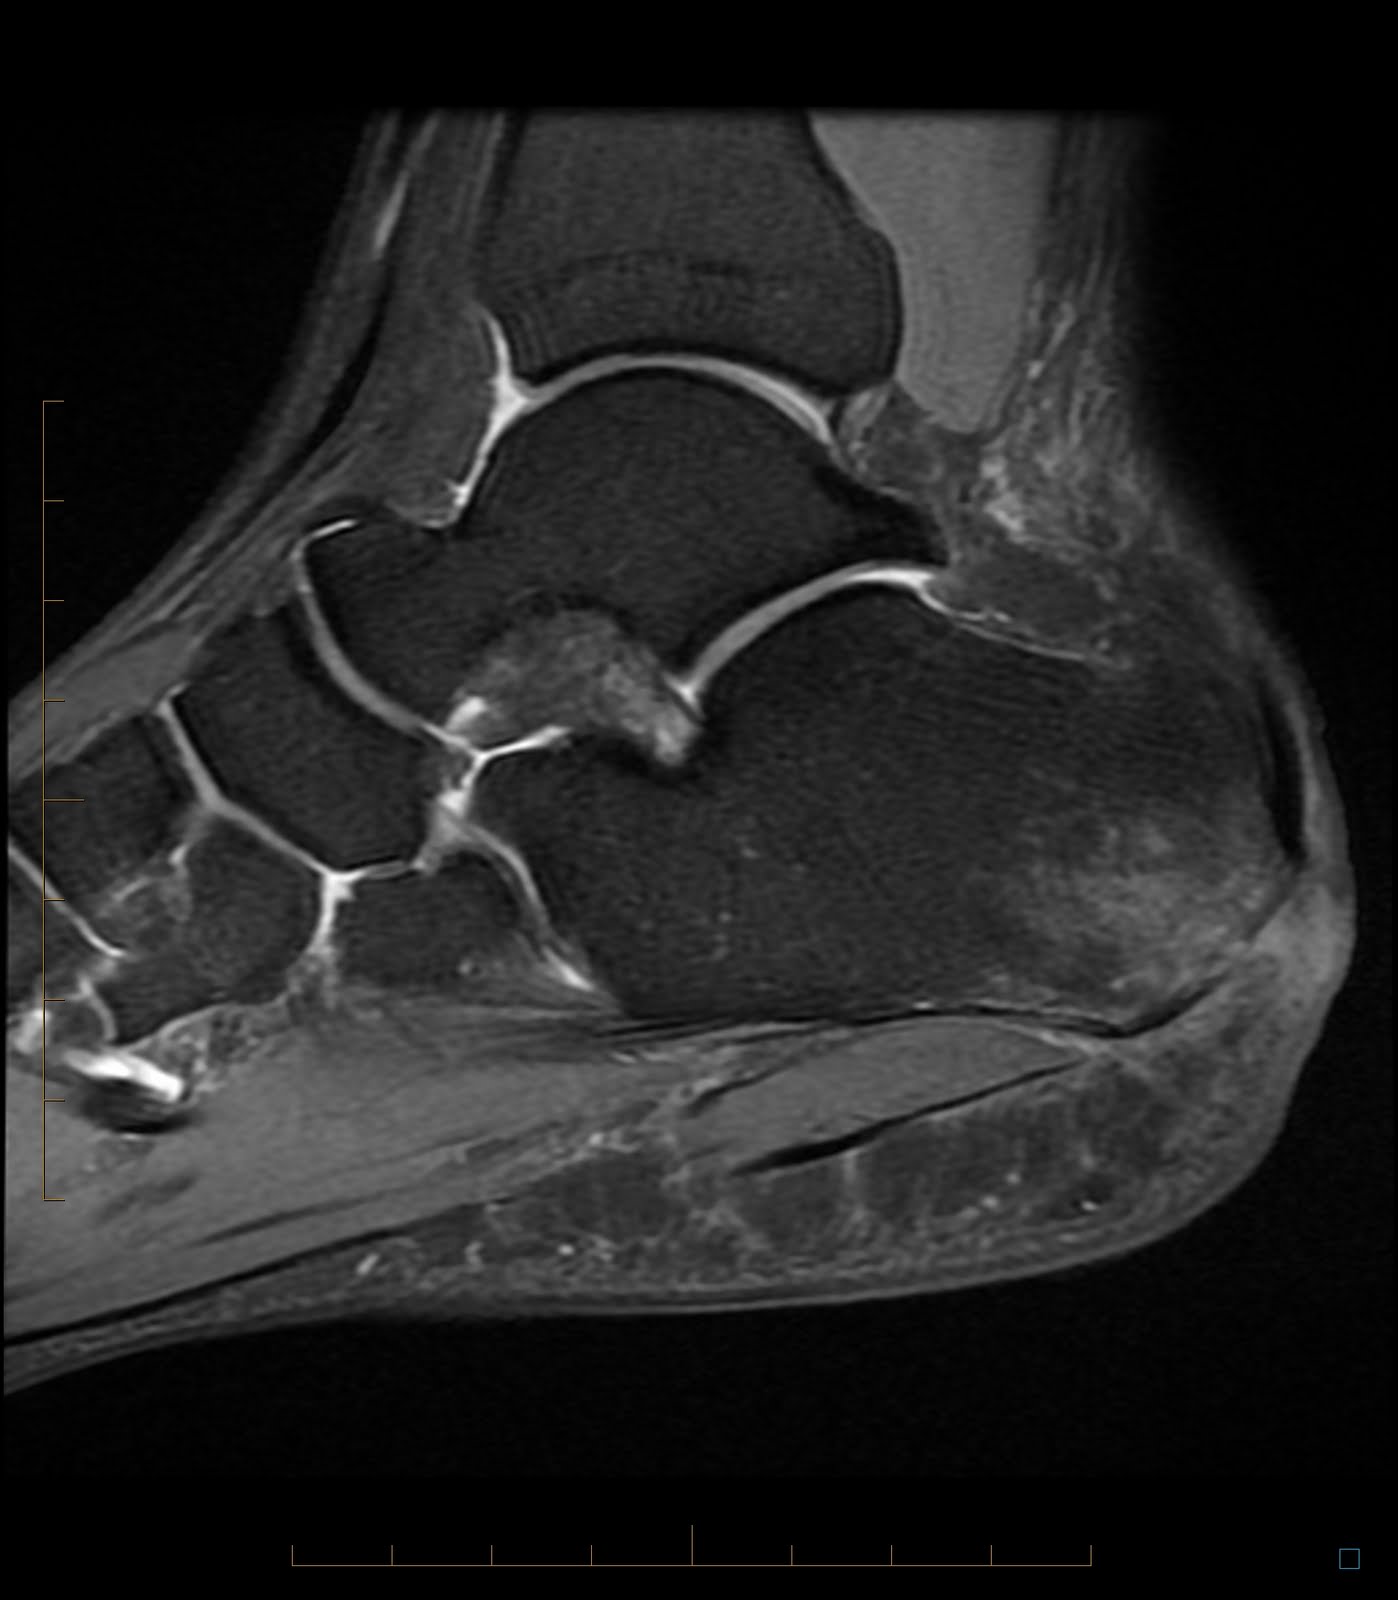

Diagnosis is made clinically with tenderness to palpation at the medial tuberosity of the calcaneus that worsens with dorsiflexion of the toes and foot.

Diagnosis can be suspected clinically with burning plantar foot pain with a positive tinel�s sign over the tibial nerve. Injury leads to reduced sensation over medial aspect of great toe. He can you have plantar fasciitis on one foot plantar fasciitis is one of the most common causes of pain in the bottom of the. It affects about 2 million individuals in the united states each year. Diagnosis is made clinically with tenderness to palpation at the medial tuberosity of the calcaneus that worsens with dorsiflexion of the toes and foot.